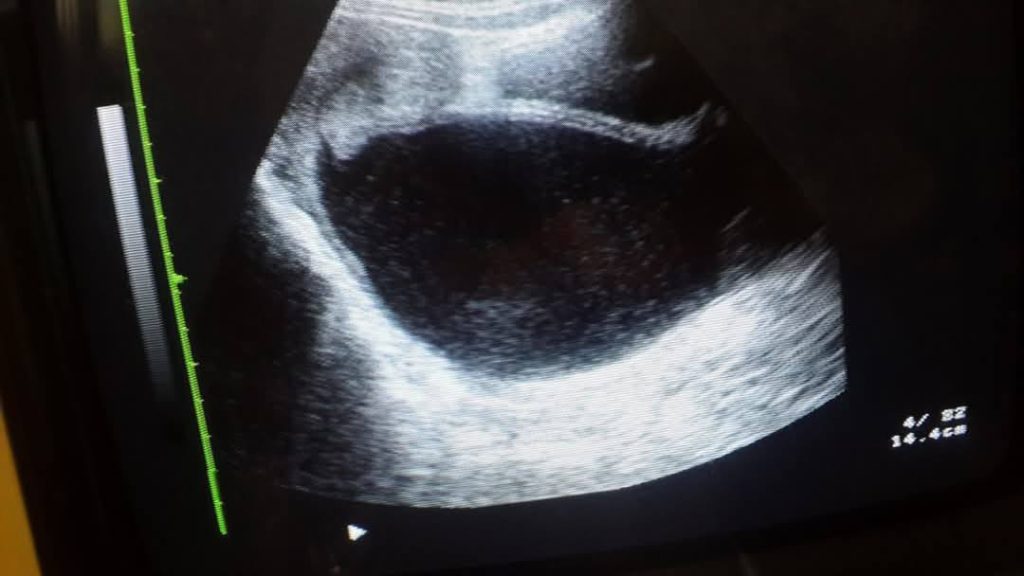

Our institutue provides high-quality ultrasound imagies for various diagnostic applications. these images serve as essential tools for accurate diagnostic and treatment planning.